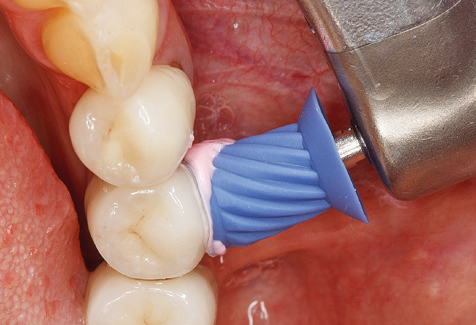

Good illumination of the working field facilitates the process considerably. The system used by the authors achieves this thanks to a 5x LED ring integrated in the handpiece. Naturally, a range of working tips for different indications is also offered. A straight, universally employable tip is the basic instrument required for machine cleaning of natural teeth (Fig. 5a and b). Curved tips, which allow access to exposed furcations, are also available for hard-to-reach areas in the posterior region (Fig. 6).

Following machine cleaning of the tooth and implant surfaces, the surfaces of the natural teeth are cleaned manually using standard hand instruments. When performing manual cleaning, particular attention must be given to maintaining the correct angle of application, appropriate sharpness, good support and working with the curette from apical to coronal. Either titanium or carbon curettes should be used for post-cleaning of the implant structures (Fig. 8). In addition to the use of ultrasonic devices, power jet devices can also be used in conservative dentistry. However, it must be taken into consideration that these procedures are not suitable for removing hard deposits and thus they cannot replace the use of hand instruments and ultrasonic instruments completely. In all cases, cleaning is followed by mechanical polishing of the accessible tooth and implant surfaces with polishing cups and polishing compounds (Fig. 9).

Fig. 9: The accessible implant and tooth surfaces are polished with polishing cups and suitable polishing compounds. – Fig. 10: Repeat instruction in the use of appropriate aids for oral hygiene at home should also form part of SPT. – Fig. 11a and b: Clinical situation 12 years after insertion of the prosthetic restoration. During this period, only a veneering ceramic fracture on tooth 47 and the requirement for endodontic treatment of tooth 12 were observed. All restorations are still functioning as intended.